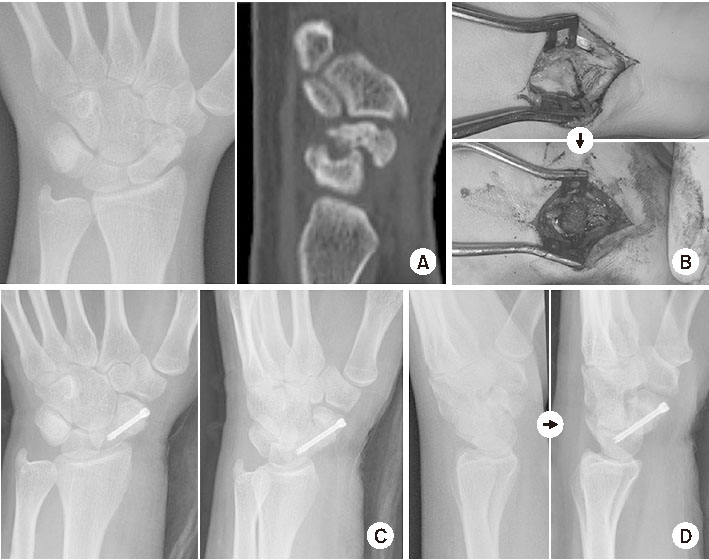

근위극 무혈성 괴사에 대한 우려로 여러 가지 혈관화 골이식술이 보고되었다. 그 중 대표적인 술식은 Zaidemberg 등이 처음 보고한 1,2-intercompartmental supraretinacular artery (ICSRA) 혈관경 골이식38)과 원위 대퇴골 내과 유리 혈관화 골이식(free medial femoral condyle vascularized bone graft, free MFC-VBG)39) 등이 있다. 1,2-ICSRA 술식은 우선 손목의 후외측으로 접근하여 주상골 불유합 부위를 노출한 뒤 소파술을 시행한다. 이후 1, 2 신전 구획 사이를 지나가는 혈관을 찾아 주변 조직과 함께 박리하고 원위 요골과 연결된 부위에서 이식 골편을 혈관경과 함께 거상한다. 골편을 불유합 위치로 옮긴 후 K-강선이나 유경 나사로 고정한다(Fig. 3).40) Free MFC-VBG는 수장측으로 주상골에 접근하여 소파술을 시행한 후 대퇴 내과에서 descending genicular artery를 혈관경으로 하는 골편을 거상한다. 혈관을 끊기 전에 골편에 출혈이 잘 되는 것을 확인한다. 불유합 부위에 이식골을 넣을 때는 혈관경이 부착된 피질골이 수장측으로 향하게 놓아 혈관이 꼬이지 않게 한다. 혈관 문합은 요골 동맥에 end-to-side로 연결하고 정맥은 vena comitans나 cephalic vein과 end-to-end로 연결한다.41)

Fig. 3

(A) Computed tomography showed a large cystic lesion in the proximal pole and severe humpback deformity. (B) Considering the vascular impairment in the proximal pole, a 1,2-ICSRA (1,2 intercompartmental supraretinacular artery) pedicled vascularized bone graft was performed. (C) Bone union was achieved, but the deformity remained.